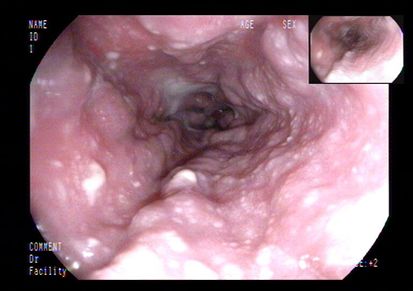

进一步检查及确诊:增强CT检查:下腔静脉肝段狭窄,内可见造影剂填充,肝脏异常强化(肝脏弥漫密度减低,门脉静脉期及平衡期显示肝脏不均匀强化,肝静脉周围呈片状明显强化,余肝实质呈轻度强化);腹部MRI:肝实质信号不均、肝静脉显示不清、腹水;肝脏病理活检:肝小叶结构未见异常,小叶中央为主的肝细胞片状退变坏死,灶性区域可见肝窦内淤血现象,形态提示缺血或淤血改变,致病因素包括药物/毒物、流出道梗阻(VOD、布加综合征)。免疫组化结果:CD34染色未见异常,CK7染色显示局部胆小管增生,局部肝细胞胆管化,HBsAg(-),特殊染色结果:Masson染色显示汇管区纤维组织增生,PAS、PAS+消化、铁、铜染色未见异常,网织纤维局部破坏。追问病史,患者起病前2月曾服用“三七粉”1月。最终诊断为吡咯生物碱相关性肝窦阻塞综合征。

上消化道内镜: